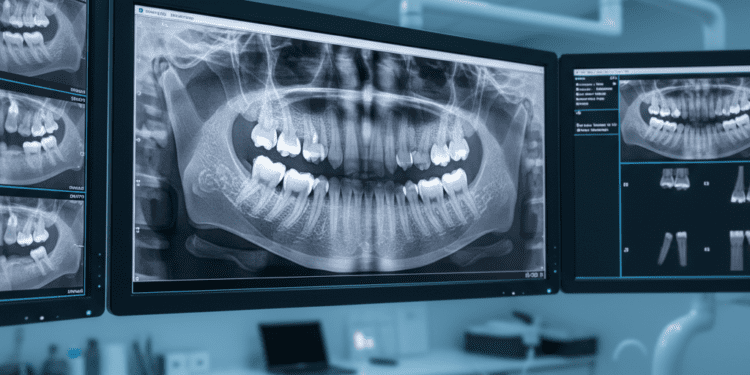

Radiografia Panorâmica: A Visão Geral

A radiografia panorâmica é uma técnica extraoral que proporciona uma visão ampla da boca, incluindo todos os dentes, maxilares, articulação temporomandibular (ATM) e até mesmo os seios maxilares. Essa abordagem é particularmente útil para ter uma noção geral da saúde bucal do paciente.

Indicações da Radiografia Panorâmica

- Planejamento de tratamento ortodôntico;

- Identificação de patologias maxilares;

- Detecção de dentes inclusos;

- Avaliação da mudança na densidade óssea em casos de doenças sistêmicas.

Benefícios Diagnósticos

A radiografia panorâmica é um exame muito valioso, pois permite que o dentista obtenha uma visão global da cavidade oral em um único clique. Isso significa que podem ser determinadas as melhores opções de tratamento, minimizando a necessidade de radiografias adicionais.